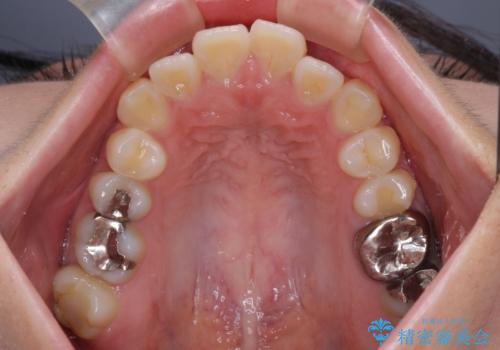

突出感の強い上顎前歯をしっかりと後方移動させるため、上顎の裏側の補助装置(リンガルアーチ)とアンカースクリューを併用しています。

上下左右の第一小臼歯を抜歯して、目立ちにくいワイヤー装置で矯正を行いました。

上下の保定用マウスピースの他に、デコボコの強かった下顎前歯にはワイヤーで保定をしています。